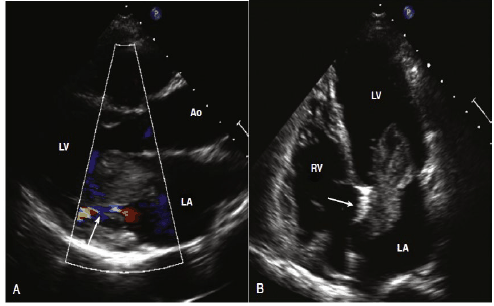

Paciente 38 anos, sem comorbidades apresentando há 7 meses episódios de sincope. Eletrocardiograma sem alterações.

Ecocardiograma abaixo:

Qual deve ser o principal diagnóstico do paciente?